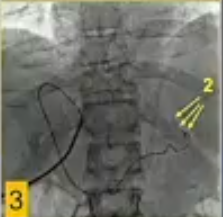

![]() ![]() US引导下经皮进入门静脉分支(瘤栓远端周围静脉),随后在瘤栓“上方”进行门静脉造影;

由于导管通过瘤栓,在血栓“下方”进行门静脉造影。

技术上的成功被定义为重新建立肝壁血流进入肝内PV分支的通畅,重新连接主PV或PV汇合处,以重建中断的门静脉血流进入整个肝脏或肝叶/节段。

男性,59岁,巨大右肝细胞癌合并PVTT伴严重静脉曲张出血,经内镜治疗无效,计划进行VesOpen手术和LGV栓塞